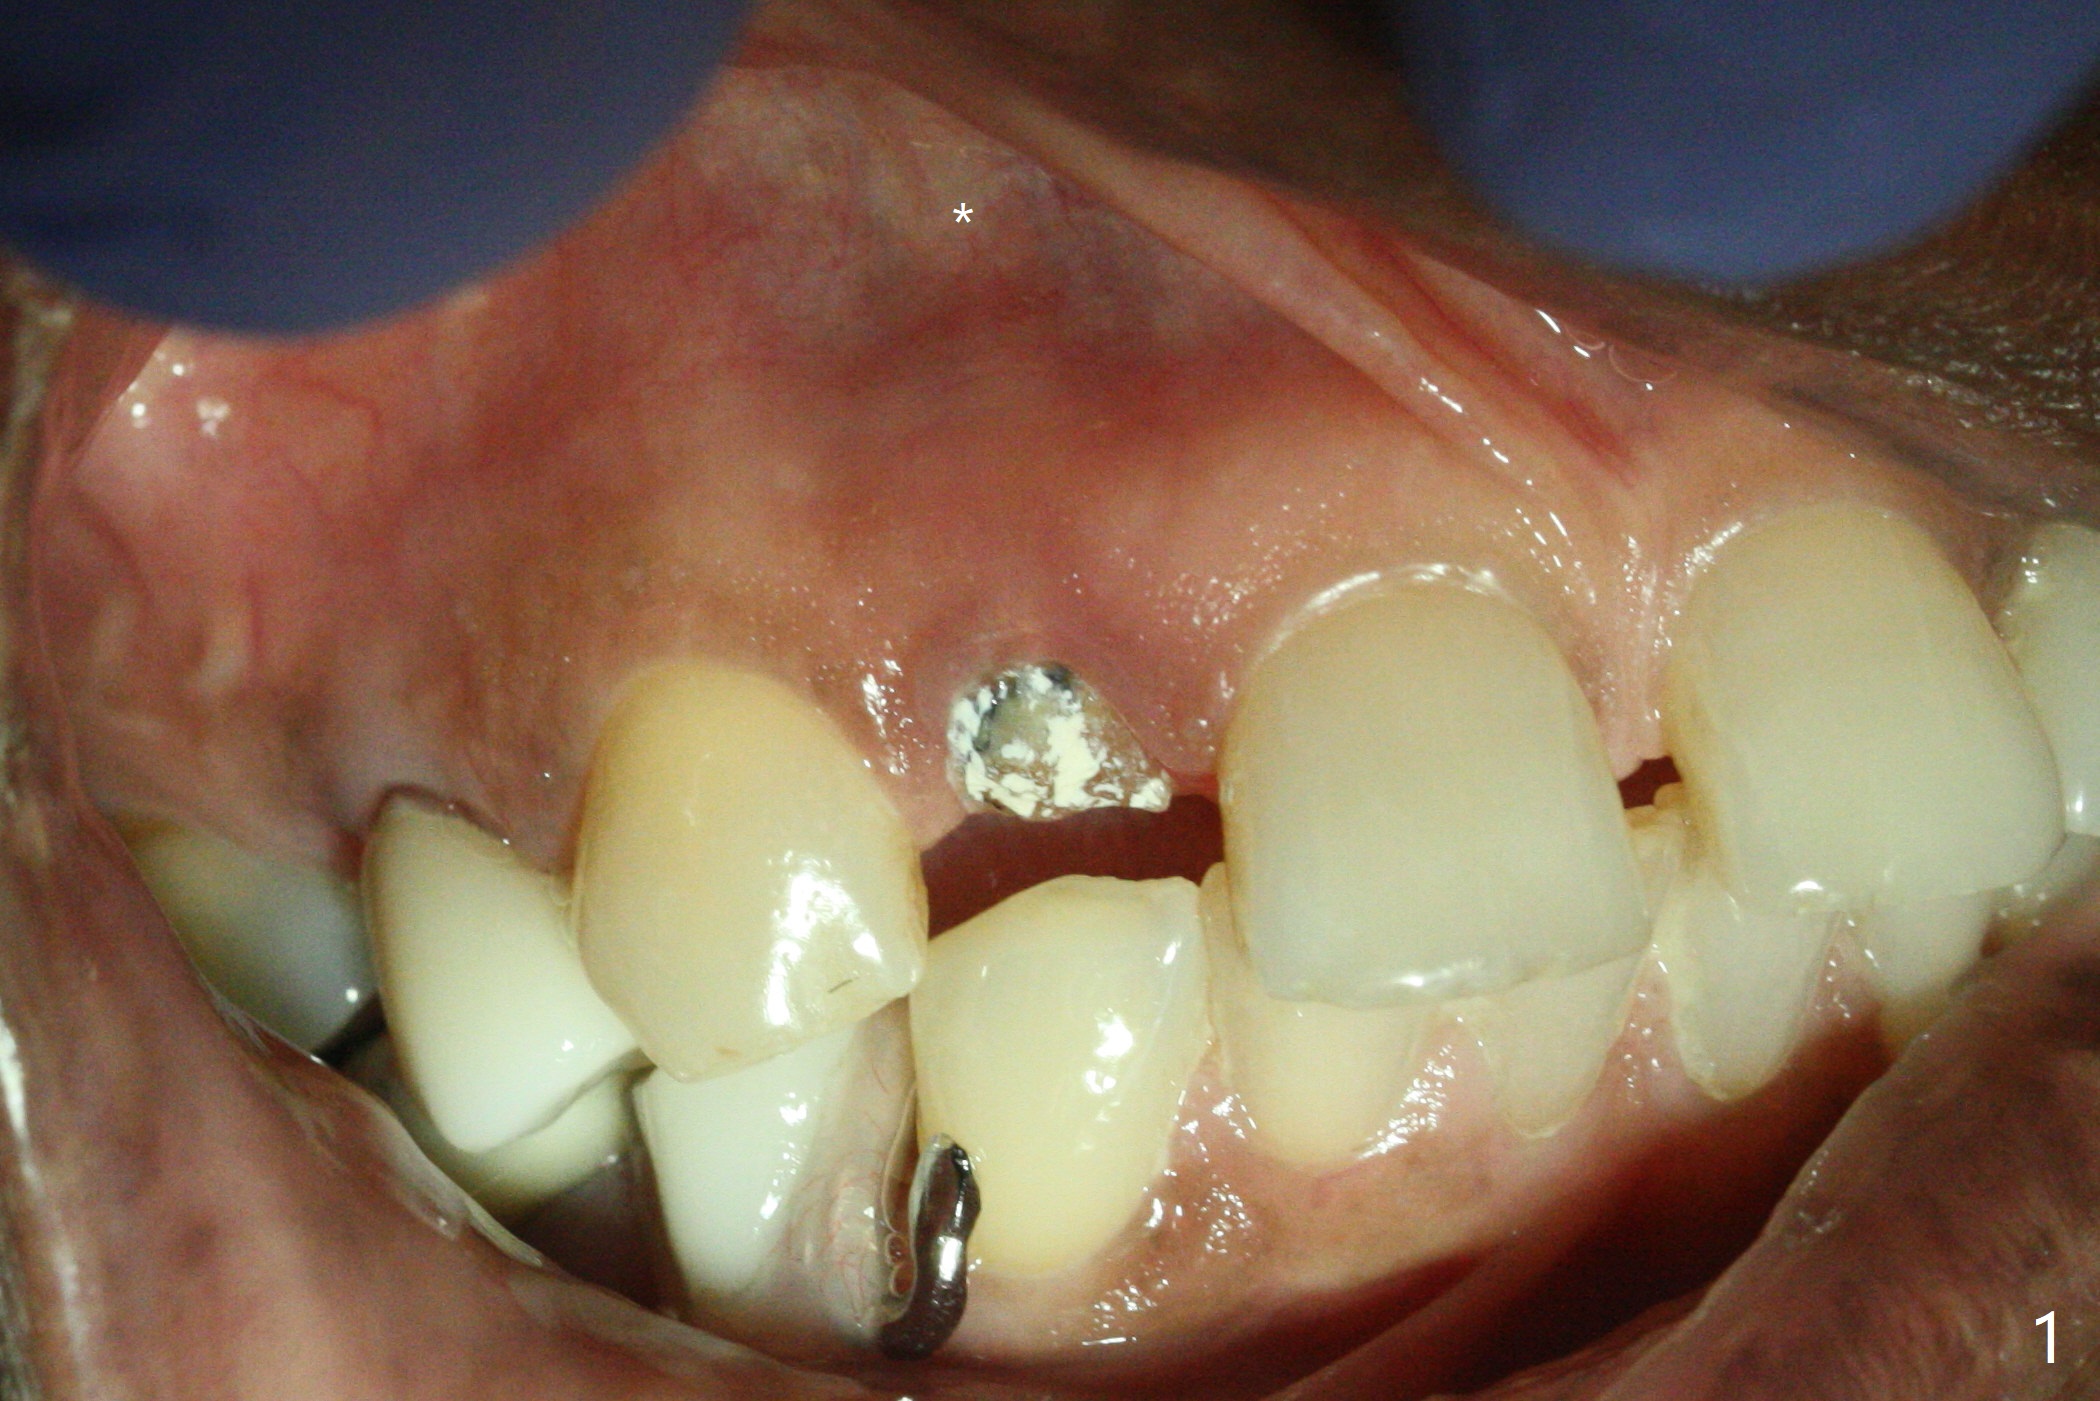

The rebonded crown at #7 debonds in a few days. There is deep anterior overbite and buccal concavity (Fig.1 *). The equigingival fracture (Fig.1,2) seems difficult to restore considering lack of posterior support (lower RPD in Fig.1). Buccal shield is tried in spite of the long root. It is not easy to tell whether the infected apex is removed due to the deep socket. In fact the apical buccal plate perforates because of use of surgical handpiece. Finally the buccal shied is removed. PA confirms the retained apex (Fig.3 *). The initial osteotomy with 1.5 mm drill in place is off trajectory (Fig.4). After adjustment of the trajectory of osteotomy (Fig.5), a 3x16(2) mm 1-piece implant is placed within normal limit (10-15 Ncm, Fig.6)). In fact bone graft is placed before (Fig.6,7 arrowhead; to repair apical buccal plate perforation) and after (Fig.6 *) implantation. The gingiva (including papillae) remains normal around the provisional 3 months postop (Fig.8). The bone graft becomes more organized 3 months postop (Fig.9), continues to do so 4.5 months postop (Fig.10) and becomes dense coronally 9 months post cementation (Fig.11: *).